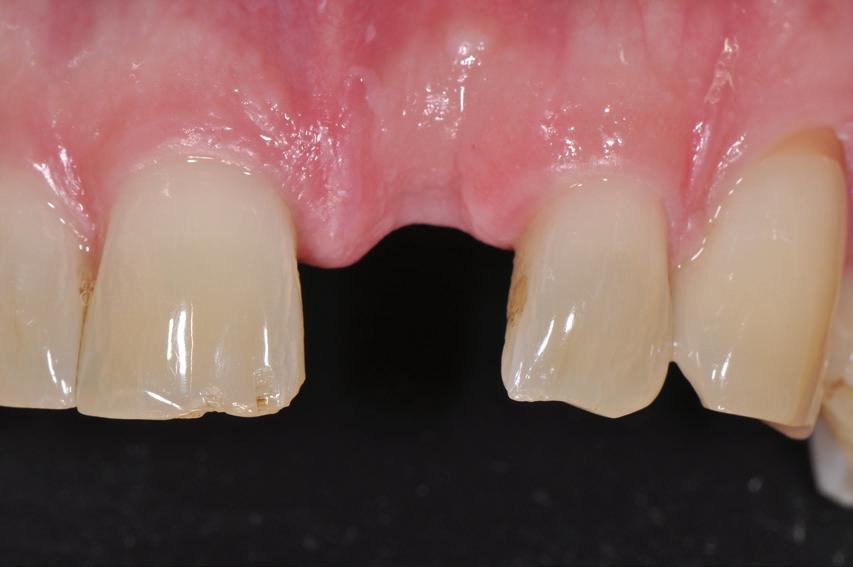

RECONFIGURAREA suportului osos implantar. În cazul prezentat, după ani de terapie ortodontică incorect executată, dezvoltarea dentară a pacientului a complicat obținerea unui zâmbet estetic. S-a reanalizat și s-a optat pentru abordare interdisciplinară care cuprinde chirurgia parodontală, un al doilea tratament

ortodontic și protetica pentru a oferi îngrijirea comprehensivă.